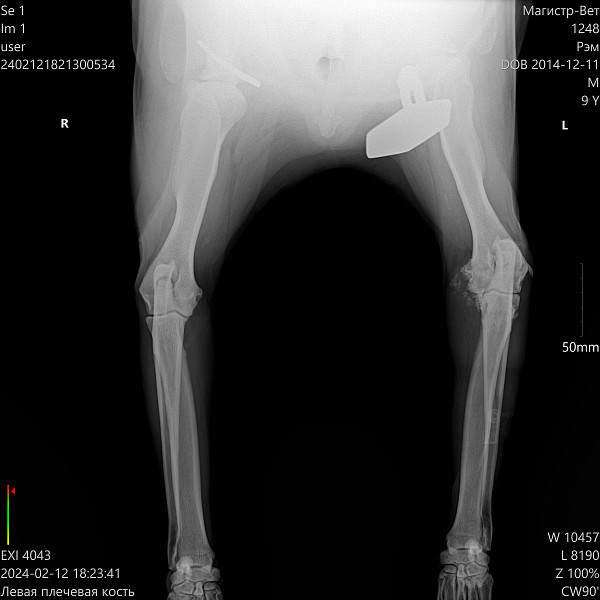

Здравствуйте! Проконсультируйте, пожалуйста. Лабрадор-ретривер, кобель, 9 лет, не кастрирован, вес 38 кг., питание сухой корм ТМ "SIRIUS", хромает на левую переднюю лапу. Рентген прилагаю. В ветклинике предлагают операцию по удалению медиального венечного отростка, при этом говорят хромота останется. Есть ли смысл в такой операции, или существуют другие способы и методы лечения? Как избавить собаку от боли? Сейчас нам назначили мелоксикам 7,5 мг: 1 день 1/2 табл. 1 р. в день, со 2 дня 1/4 табл. 1 р. в день. всего 6 дней. А дальше что делать? Это ведь не панацея.

Пес очень активный, любит гулять, как можно помочь ему с таким суставом? Какие вообще прогнозы при таком рентгене?

Добрый день. У вашей собаки к сожалению существенные дегенеративные изменения локтевого сустава. Оперативное вмешательство с целью удаления венечного отростка может не дать положительного эффекта, но может слегка облегчить состояние. Сустав не восстановить! Можно под контролем узи ввести в полость сустава противовоспалительные препараты и гиалуроновую кислоту, но для начала проконсультируйтесь с ортопедом. Худеть! Ограничение физических нагрузок.